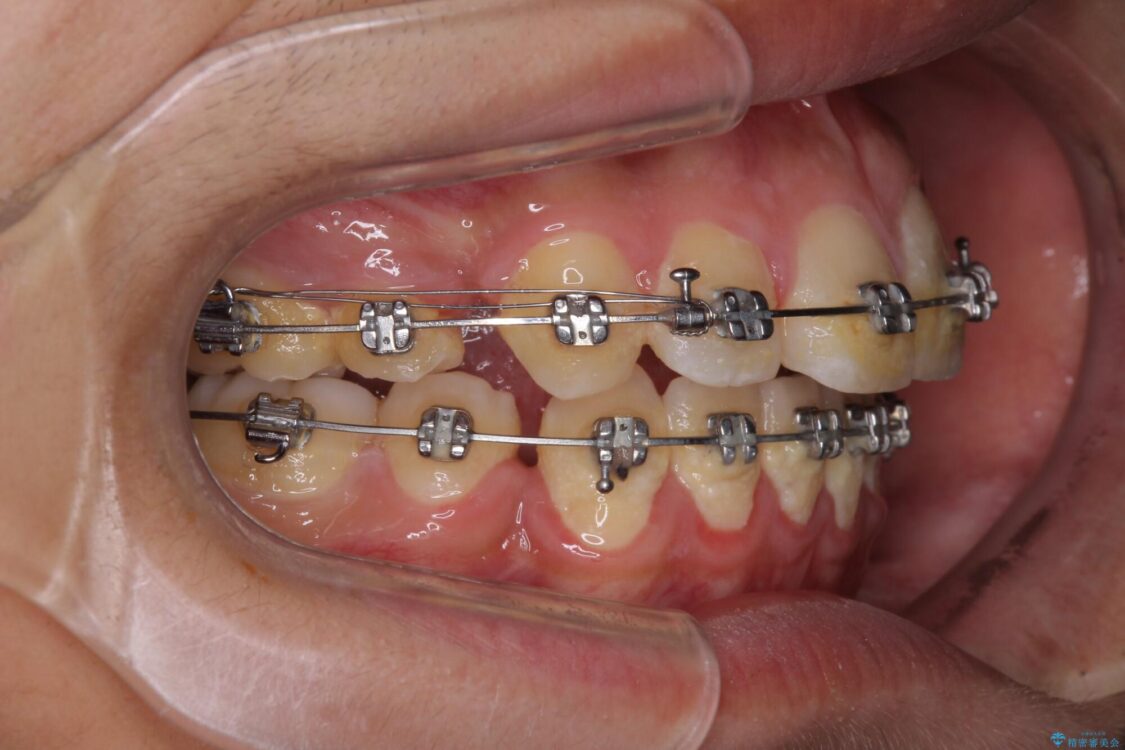

治療途中

• 膨らんだ口元 ワイヤー装置での抜歯矯正 治療途中画像

メタルブラケット

上下前歯が著しく前突している状態であったので、上下左右の第1小臼歯4本を抜歯し、ワイヤー装置にて矯正治療を行うこととしました。